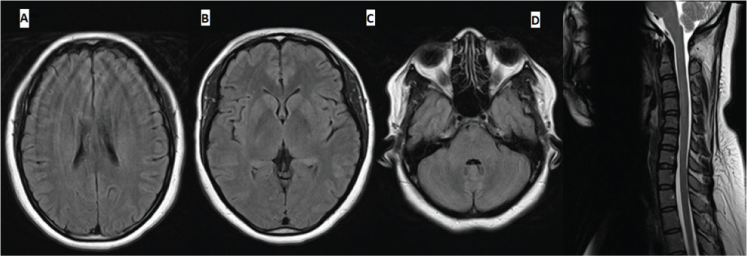

The differential diagnosis included postvaccination acute disseminated encephalomyelitis (ADEM)–like multifocal demyelination and NMOSD. The patient was treated with five cycles of plasma exchange followed immediately by 2 days of intravenous immunoglobulin (IVIG), 1 g/kg per day, with subsequent initial improvement of tremor and leg weakness followed by resolution of vertigo, vomiting, and sphincteric dysfunction. Corticosteroids were not used to avoid their potential teratogenic effect in the first trimester and to avoid premature rupture of membranes.1,2 Treatment with plasma exchange was favored given its superior efficacy in NMOSD,3 and IVIG was added given the potential value in postvaccination demyelination.4 Repeated MRI after treatment showed complete resolution of the cervical lesion and near resolution of the brain abnormalities (Figure 2).

Axial fluid-attenuated inversion recovery magnetic resonance images (MRIs) of brain (A-C) and sagittal T2-weighted MRI of cervical spine (D) after treatment